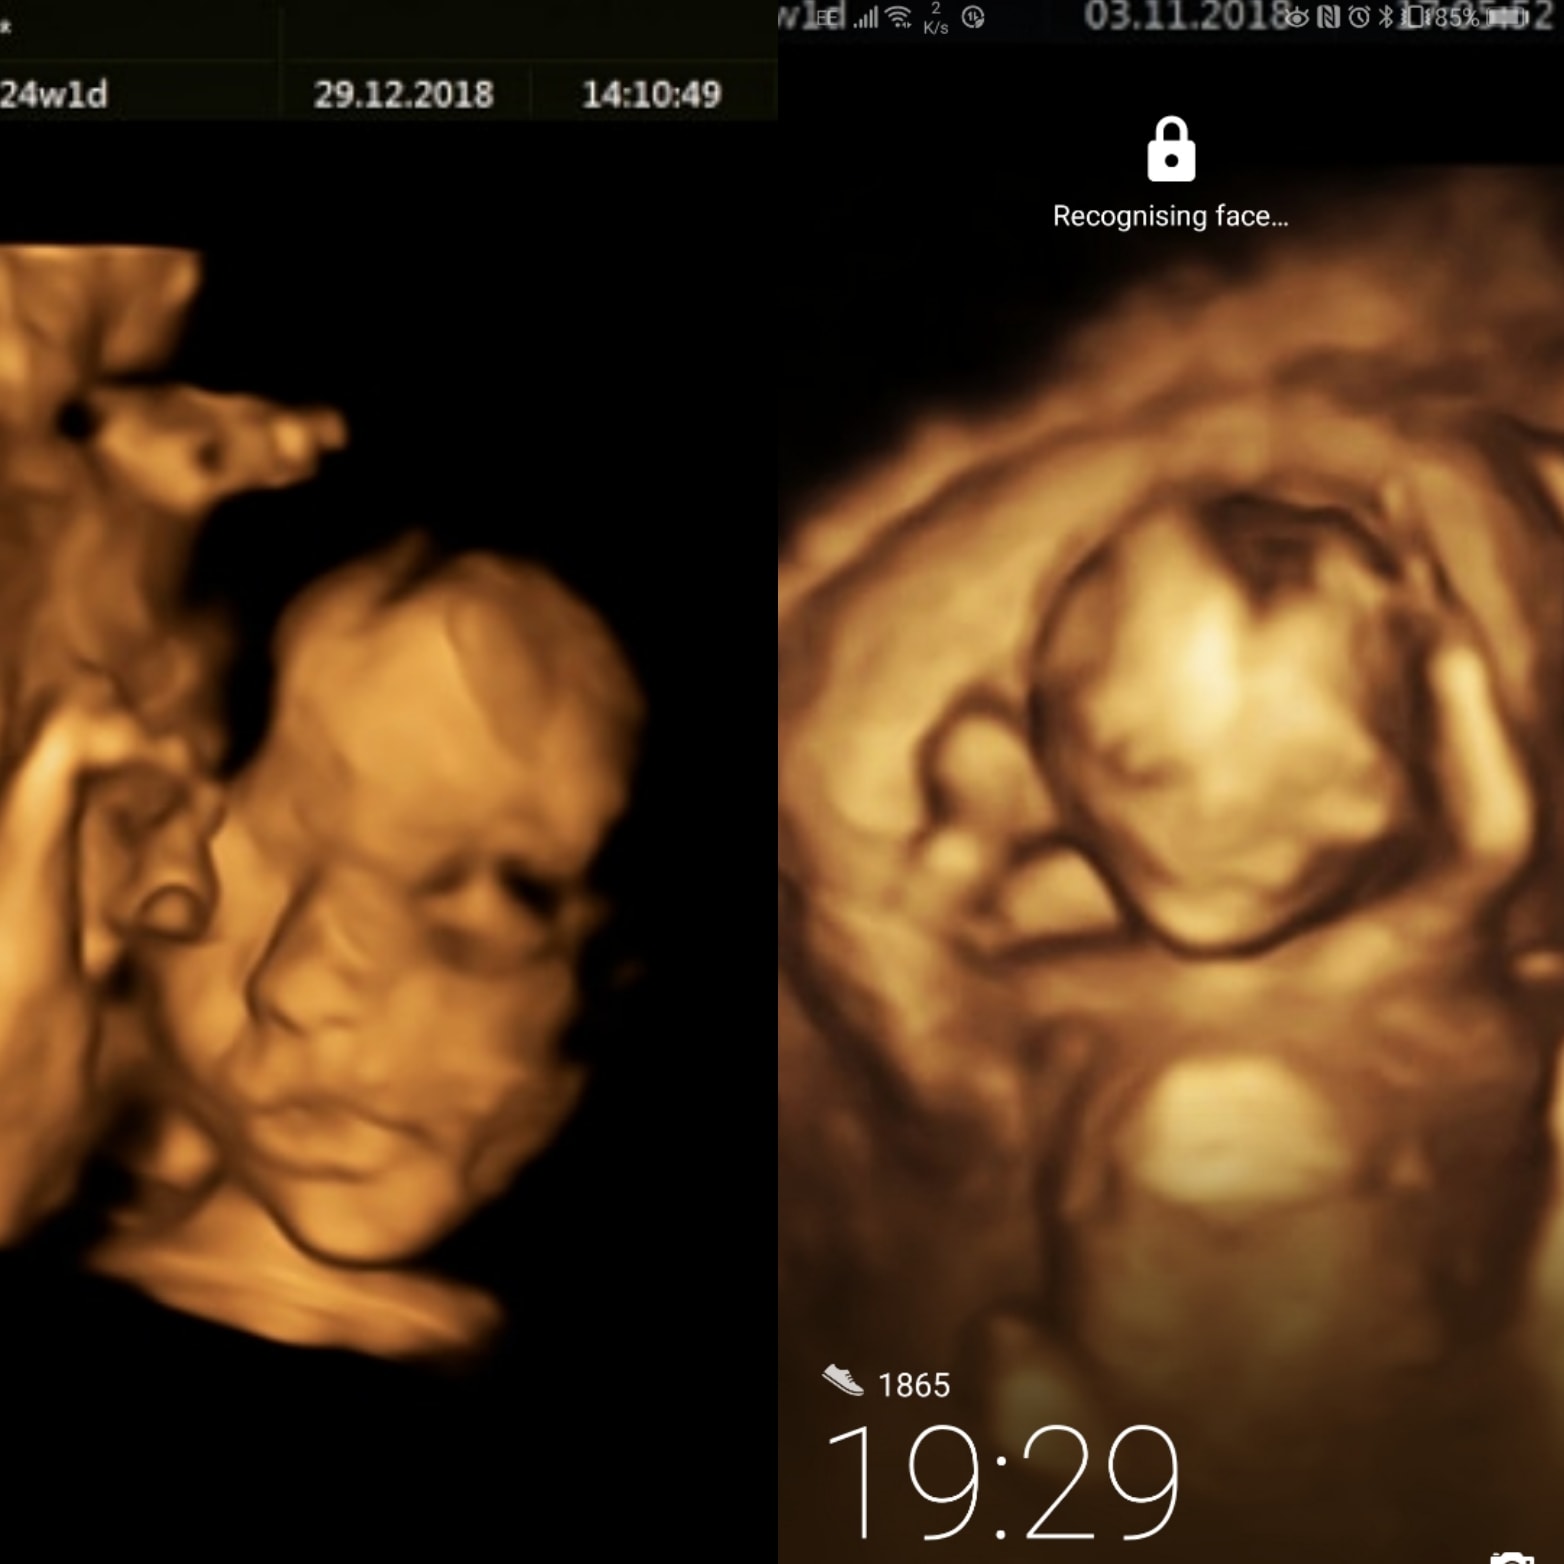

▼最後在懷孕24周時終於接受手術,讓來自倫敦和比利時的醫生負責動手術。

▼醫生首先幫Bethan做全身麻醉,然後在子宮位置開刀將胎兒取出。

▼接著就開始調整好胎兒的脊柱位置,還要加強保護,確認完成所有步驟後再把寶寶放回母體繼續孕期。根據醫生解釋,這項手術的主要目的是防止情況惡化,只有這樣才能在寶寶出生後再動其他脊柱手術,讓效果更佳。